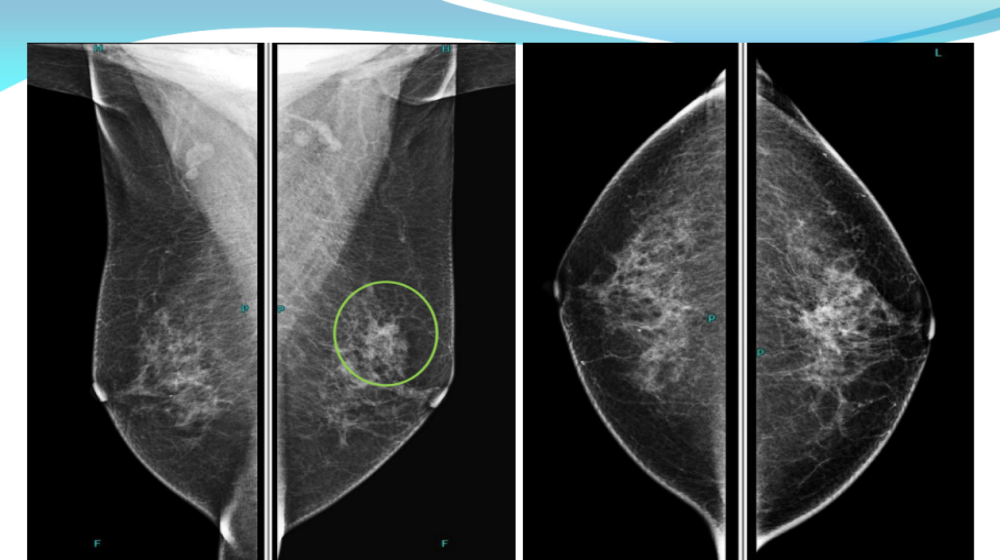

(3)非高危女性从40周岁开始,每年做一次乳腺钼靶筛查;对于有乳腺癌家族史者、未育、月经初潮早等高危因素的女性从35周岁开始,每年做一次乳腺钼靶筛查。而且,女性最好选择在经期结束3-7天进行乳腺钼靶检查。数字化乳腺钼靶是目前国际推荐的乳腺癌筛查手段。

乳腺X线检查是提高乳腺癌早期诊断的主要手段。全数字化平板乳腺机在早期临床诊断乳腺疾病中具有举足轻重的地位。